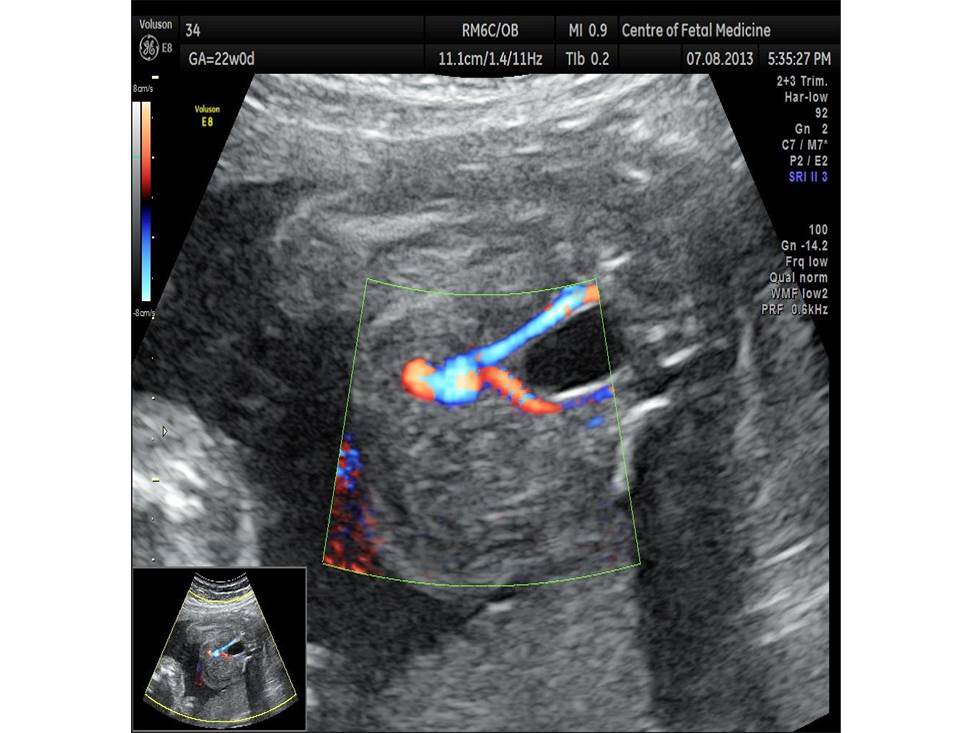

Вопрос 5

Проанализируйте изображения плода в 22 недели и установите диагноз